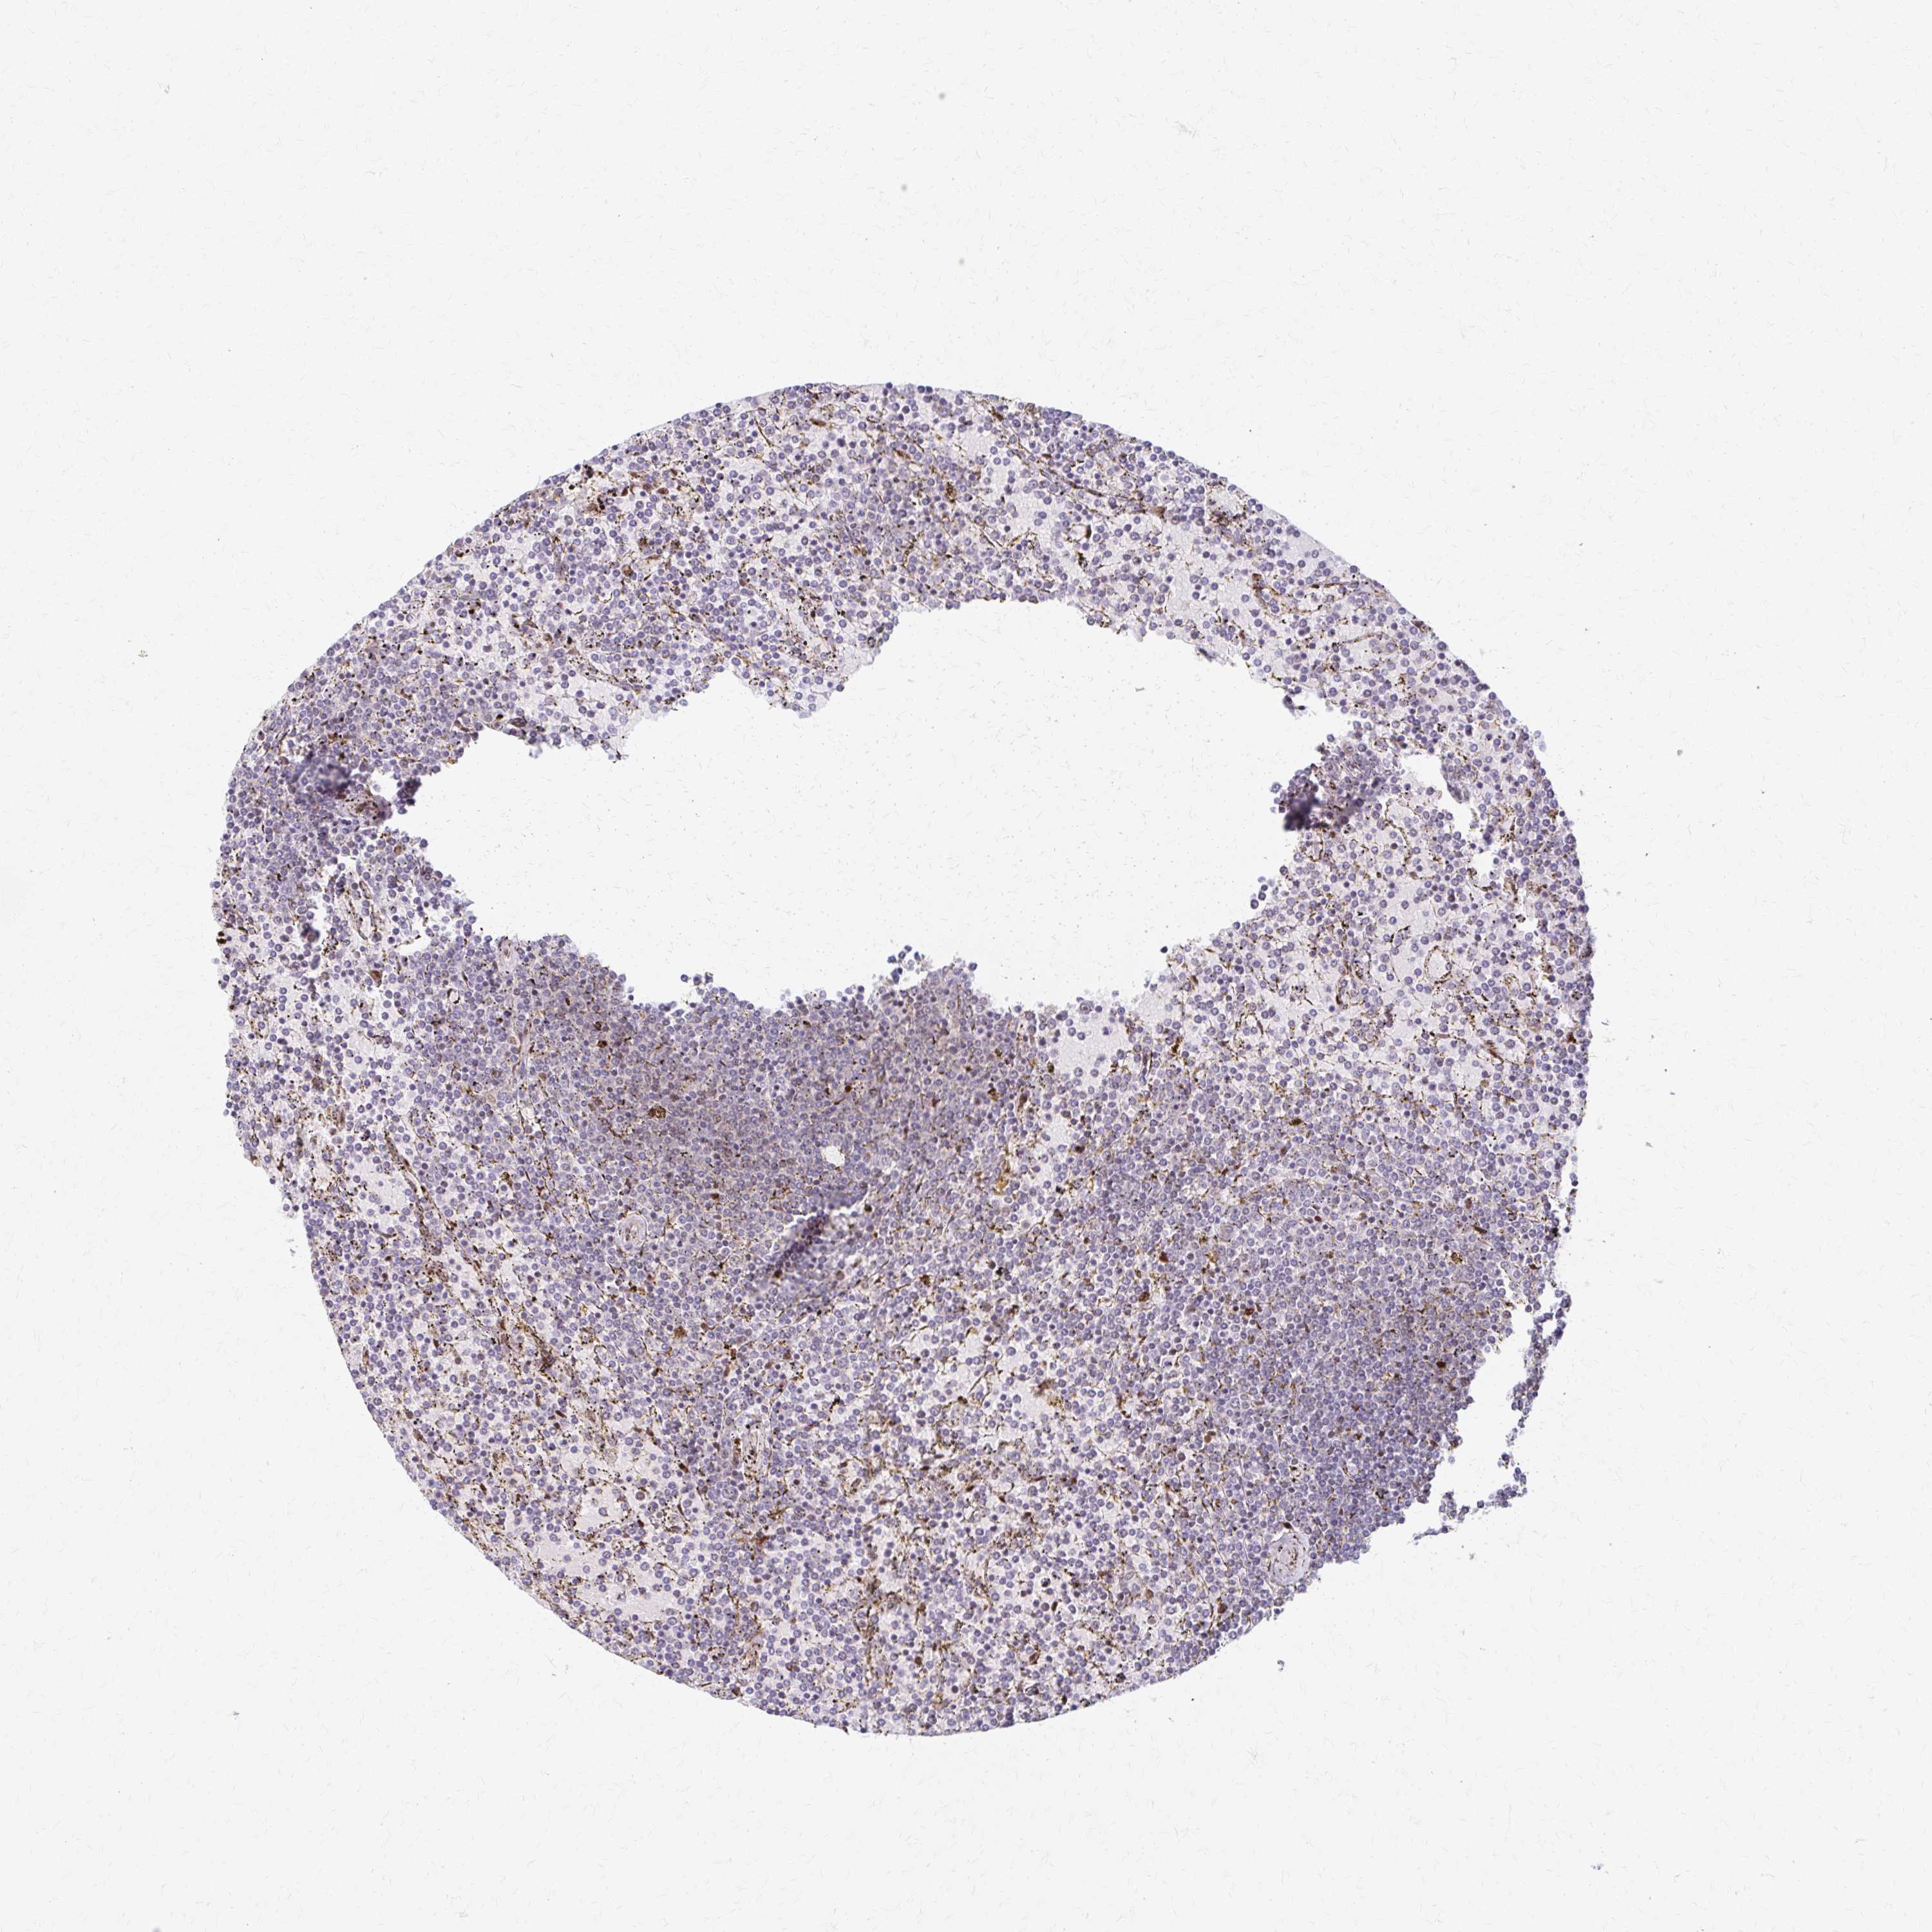

LYMPHOMA - Protein expressioni

A mouse-over function shows sample information and annotation data. Click on an image to view it in a full screen mode. Samples can be filtered based on level of antibody staining by selecting one or several of the following categories: high, medium, low and not detected. The assay and annotation is described here.

Antibody stainingi

Antibody staining in the annotated cell types in the current human tissue is reported as not detected, low, medium, or high, based on conventional immunohistochemistry profiling in selected tissues. This score is based on the combination of the staining intensity and fraction of stained cells.

Each image is clickable and will lead to virtual microscopy that enables deeper exploration of all samples and also displays staining intensity scores, fraction scores and subcellular localization as well as patient and tissue information for each sample.

Antibody HPA049824

Staining

High

Medium

Low

Not detected

Intensity

Strong

Moderate

Weak

Negative

Quantity

>75%

75%-25%

<25%

None

Location

Nuclear

Cytoplasmic/membranous

Cytoplasmic/membranous,nuclear

Malignant lymphoma, non-Hodgkin's type, Low grade